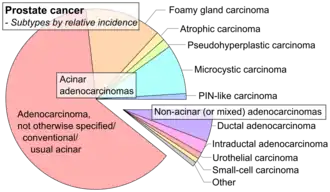

A histopathologic diagnosis of prostate cancer is the discernment of whether there is a cancer in the prostate, as well as specifying any subdiagnosis of prostate cancer if possible. The histopathologic subdiagnosis of prostate cancer has implications for the possibility and methodology of any subsequent Gleason scoring.[1] The most common histopathological subdiagnosis of prostate cancer is acinar adenocarcinoma, constituting 93% of prostate cancers.[2] The most common form of acinar adenocarcinoma, in turn, is "adenocarcinoma, not otherwise specified", also termed conventional, or usual acinar adenocarcinoma.[3]

| Subdiagnosis | Relative incidence | Image | Microscopic characteristics | Immunohistochemistry | Gleason scoring | ||

| Acinar adenocarcinoma - 93%[2] |

Adenocarcinoma (not otherwise specified/ conventional/ usual acinar)[3] |

77%[notes 2] | 54%[notes 2] | _with_glomeruloid_glands.jpg)

| Foamy gland carcinoma | 17%[5][notes 1] | 13–23%[5][notes 1] | Based on architecture, discounting foamy cytoplasms[1] | ||||

| Atrophic carcinoma | 2%[5][notes 3] | 16%[5][notes 3] | Tumorous glands: | As usual[1] | |||

| Pseudohyperplastic carcinoma | 2%[5] | 11%[5] |

| Microcystic carcinoma | 11%[5] | On (usually) adjacent acinar adeocarcinoma[6] | |||||

| PIN-like | 1.3%[7] |

| Non acinar (or mixed acinar/ non-acinar) adenocarcinoma |

Ductal adenocarcinoma | 3% to 12.7%[8][notes 1] |

| Intraductal adenocarcinoma | 2.8%[10] |  H&E and CK5/6 |

| Urothelial carcinoma | 0.7 to 2.8%[12] |

| Small-cell carcinoma | 0.3–2%[14][15][notes 1] |

| Mucinous adenocarcinoma | 0.2%[12] | _with_individual_well-formed_glands_and_minor_component_of_cribriform_glands_floating_in_extracellular_mucin.jpg)

| Signet-ring adenocarcinoma | 0.02%[16] |

| Basal-cell carcinoma | 0.01%[17] | Basaloid tumor:

These constitute 93% of prostate cancers.[2]